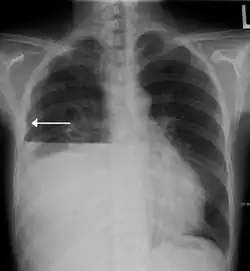

| A hydropneumothorax with a white arrow pointing to the lung's pleura | |

Hydropneumothorax is defined as the presence of both air and fluid within the pleural space.[1] An upright chest x-ray will show air fluid levels. The horizontal fluid level is usually well defined and extends across the whole length of one of the hemithorax.